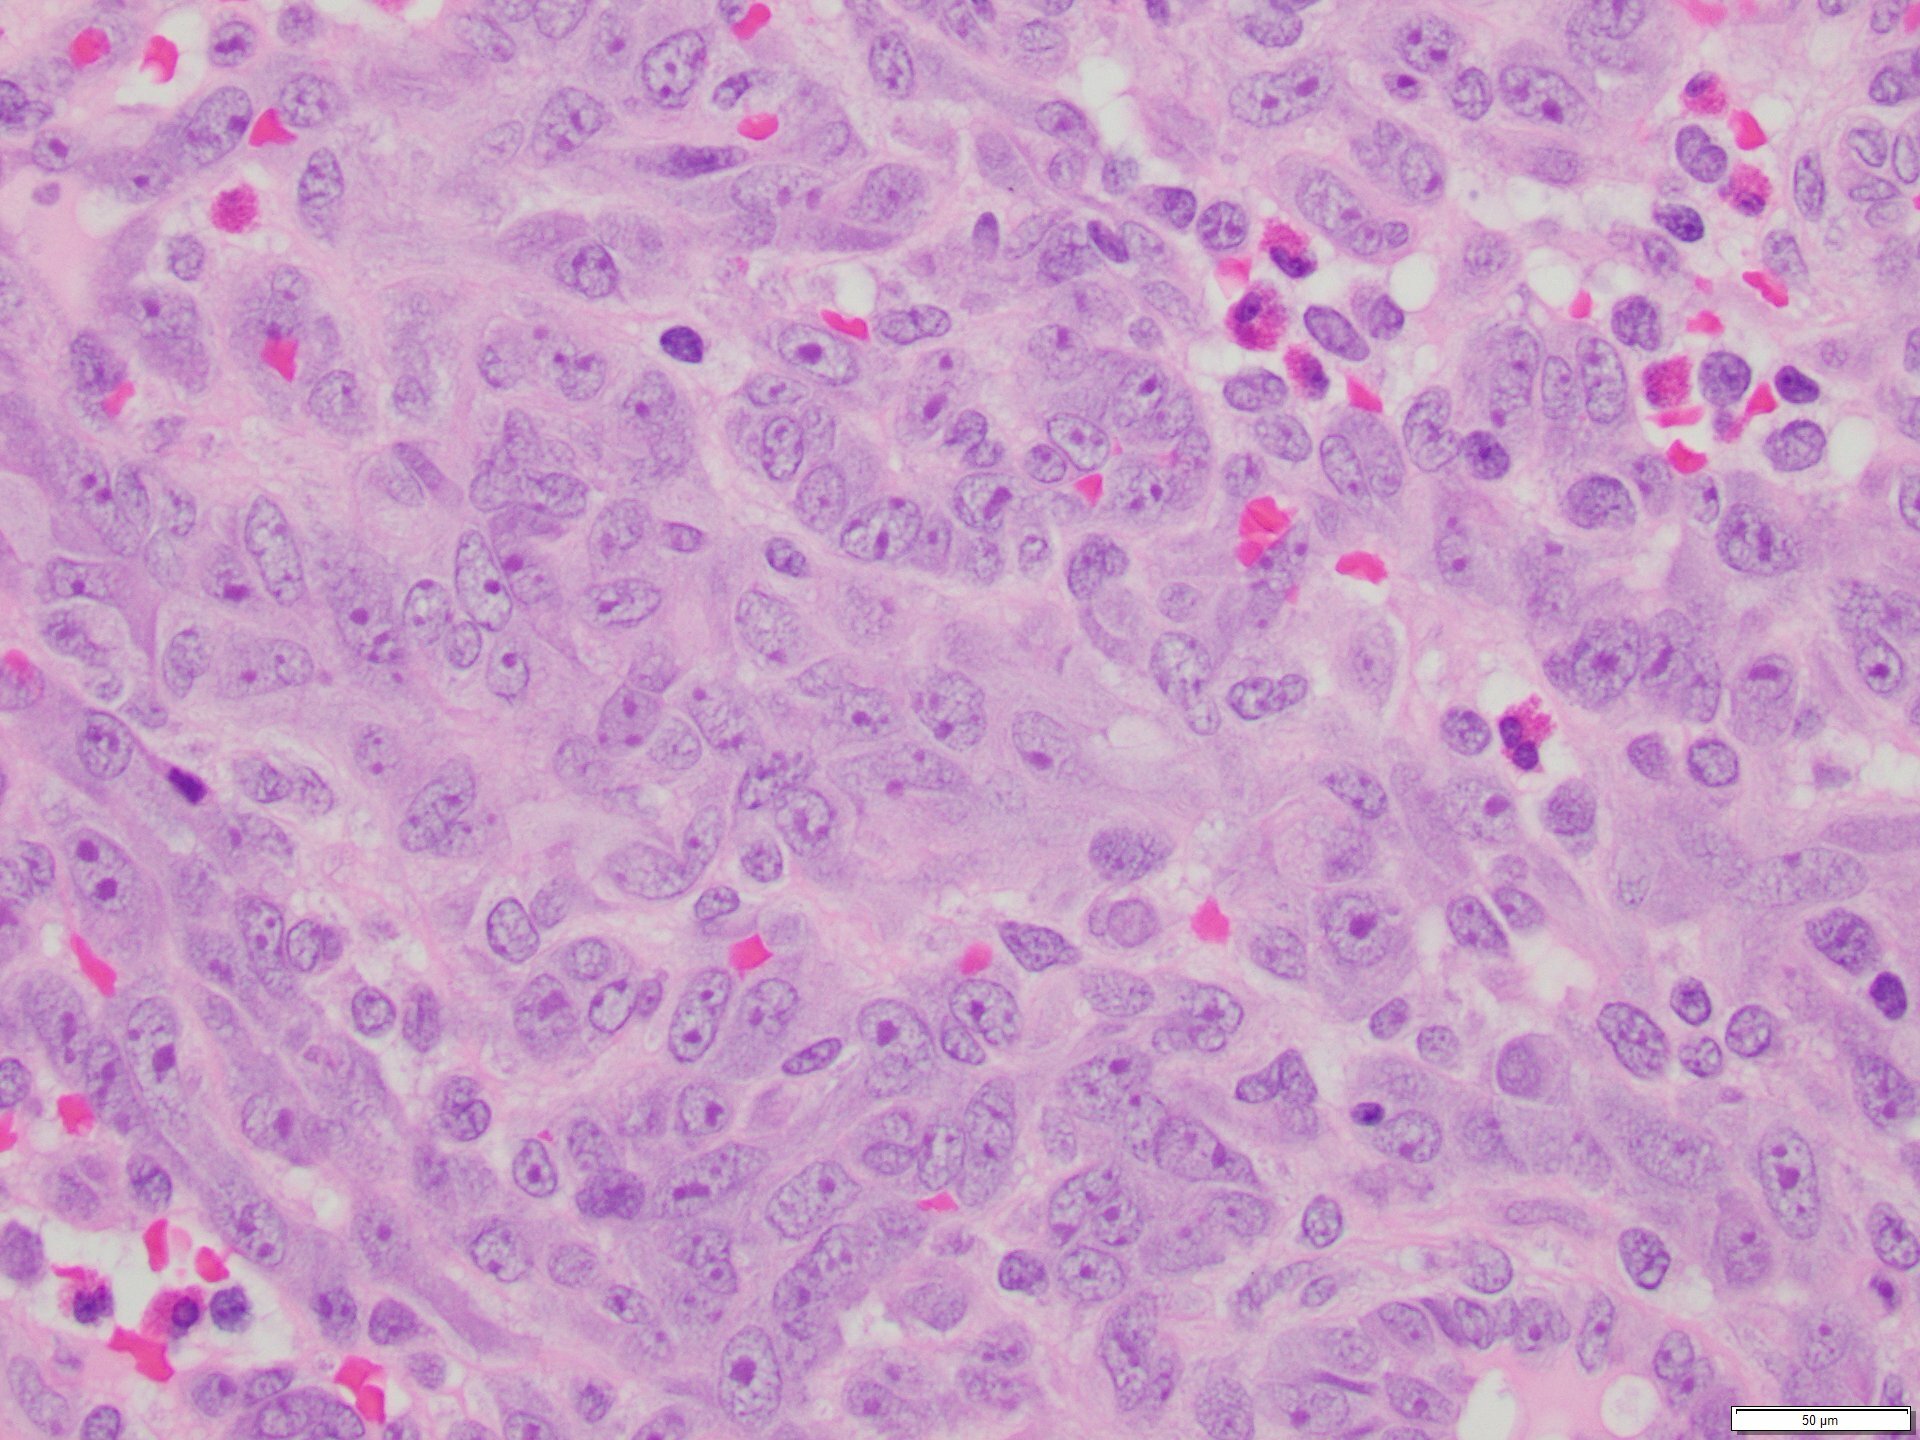

The skin lesion was completely excised and sent to pathology for diagnosis (Figures 1-3). The lesion is hypercellular with an infiltrative, predominantly solid, growth pattern in the dermis and subcutaneous tissue. It is highly vascular and has complex anastomosing and poorly formed vascular channels. The tumor cells are large, pleomorphic, have vesicular chromatin, and prominent nucleoli. There are frequent mitoses and extravasated red blood cells throughout. Immunohistochemistry shows the tumor cells are diffusely positive for ERG (Figure 4) and c-MYC (Figure 5) while negative for pan-cytokeratin (Figure 6) and GATA3. Subsequently, the patient underwent a left total mastectomy.